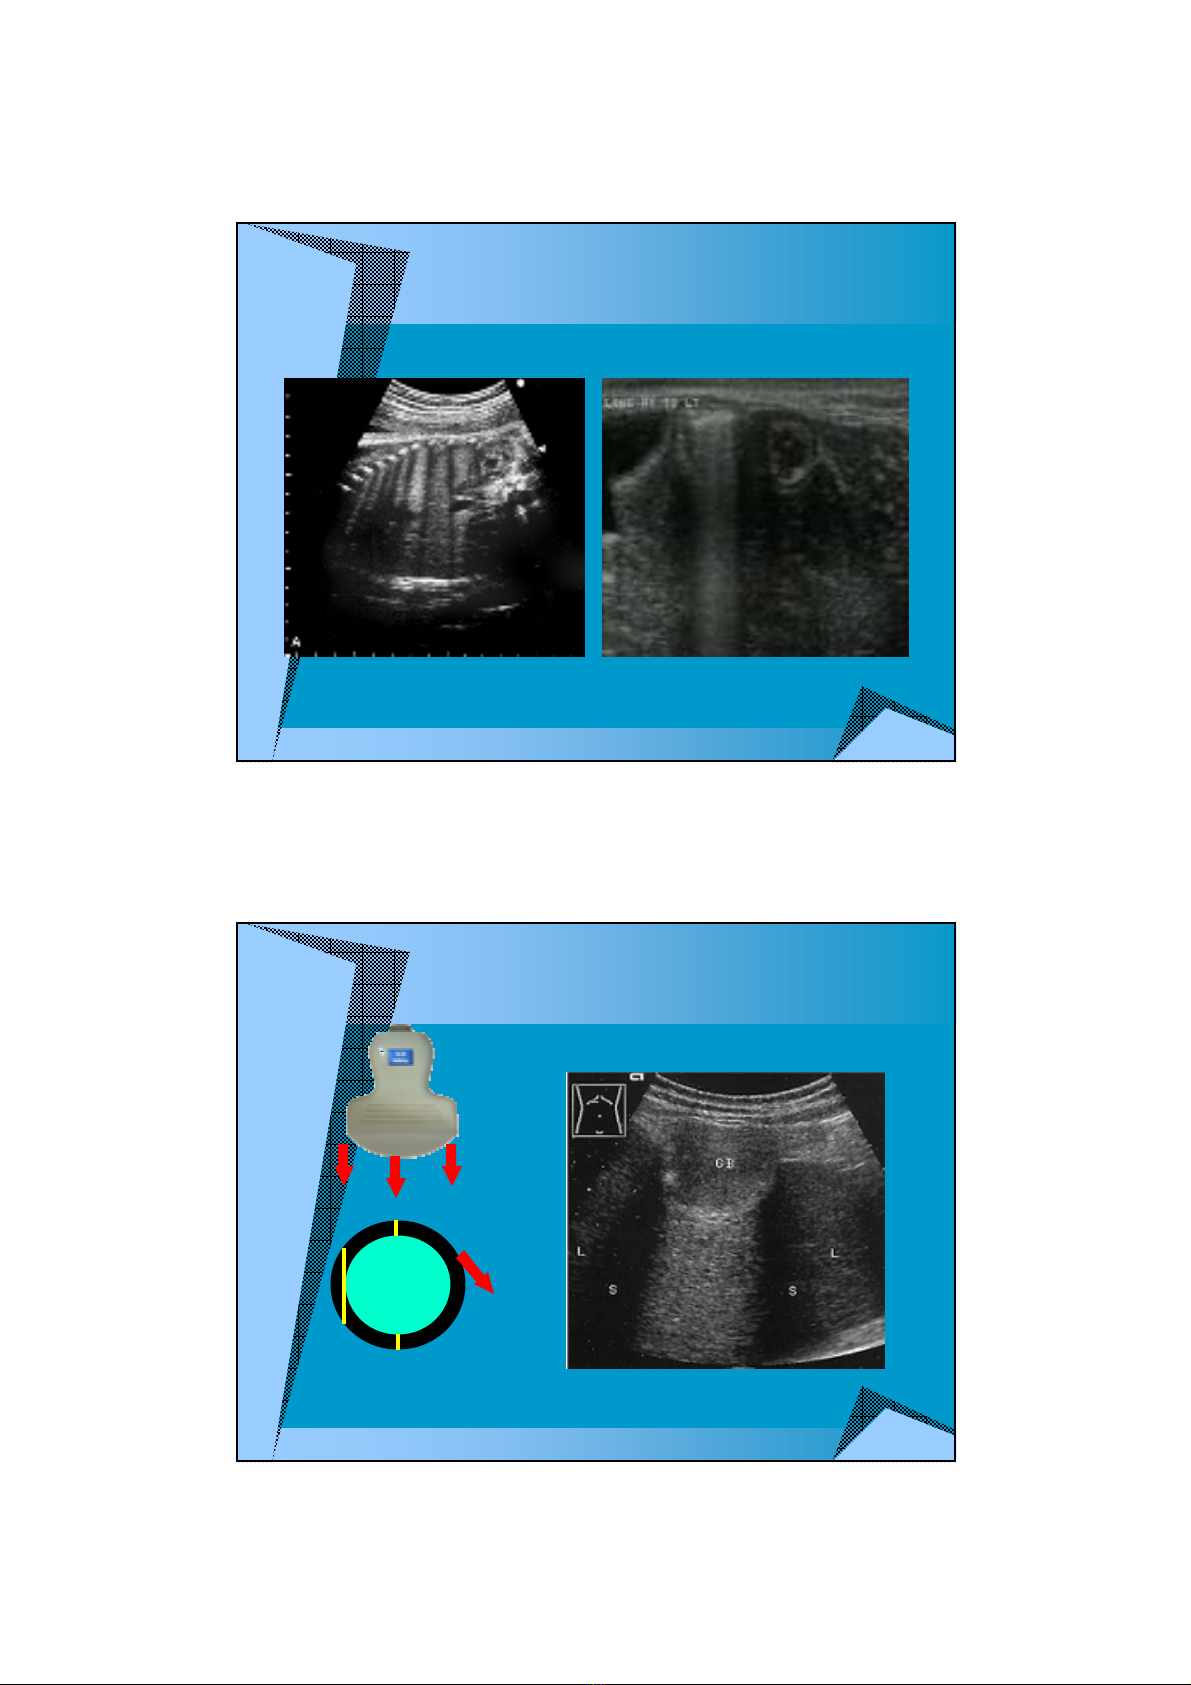

NG LNG

NG LNG BÊN

a